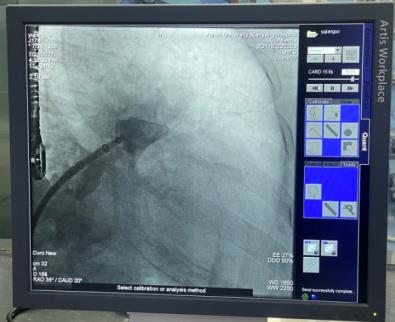

穿刺房間隔后置入6F豬尾導管,于CAU20°,RAO35°進行左心耳造影,可見左心耳為大角度反雞翅形,測量左心耳開口26mm,深度25mm。各位在線的專家有張玉順教授、宋治遠教授、胡浩教授等,進行了熱烈討論后,一致認為該例手術難度較大,封堵傘不易釋放。

經(jīng)過仔細讀圖,發(fā)現(xiàn)左心耳下葉可作為封堵主軸向,該方向避免了大角度反折,但深度略淺,手術難度仍是不小。最終選取30mmWATCHMAN封堵器。